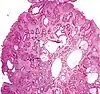

| Tubular Adenoma (Villous, Tubulovillous) | Colorectal | Tubular glands with elongated nuclei (at least low-grade atypia) | Yes | ![]() |

|